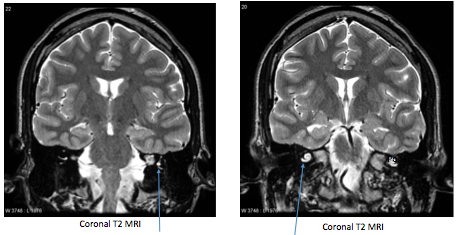

What are the arrows pointing to on the image?

What two important structures are shown in the image?

Label the image

How does neural tissue appear on a T2 MRI after a stroke?